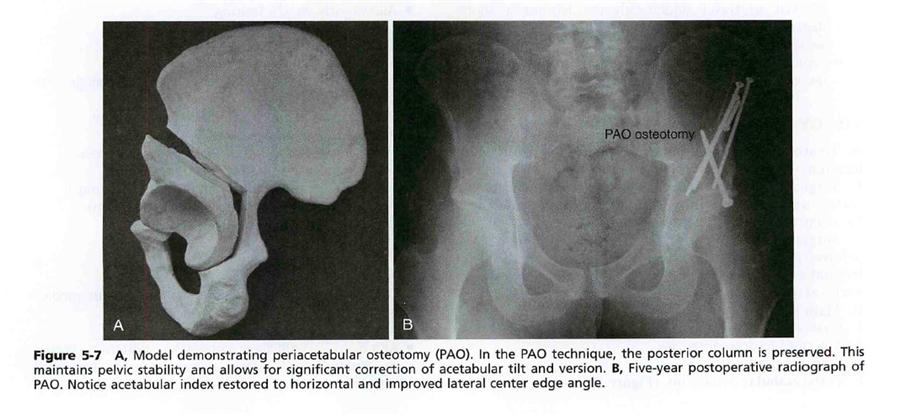

4. Ganz의 경우 비구를 아에 4방향 모두 (직하 좌골, 치골, 비구 상방장골, 비구 후면) 떼어내서 전외측으로 회전하여 교정하기 때문에 많이 위험하고 어렵지만 true pelvis를 유지하게 해줘서 (골반모양유지), 출산에 유리한 방법입니다.